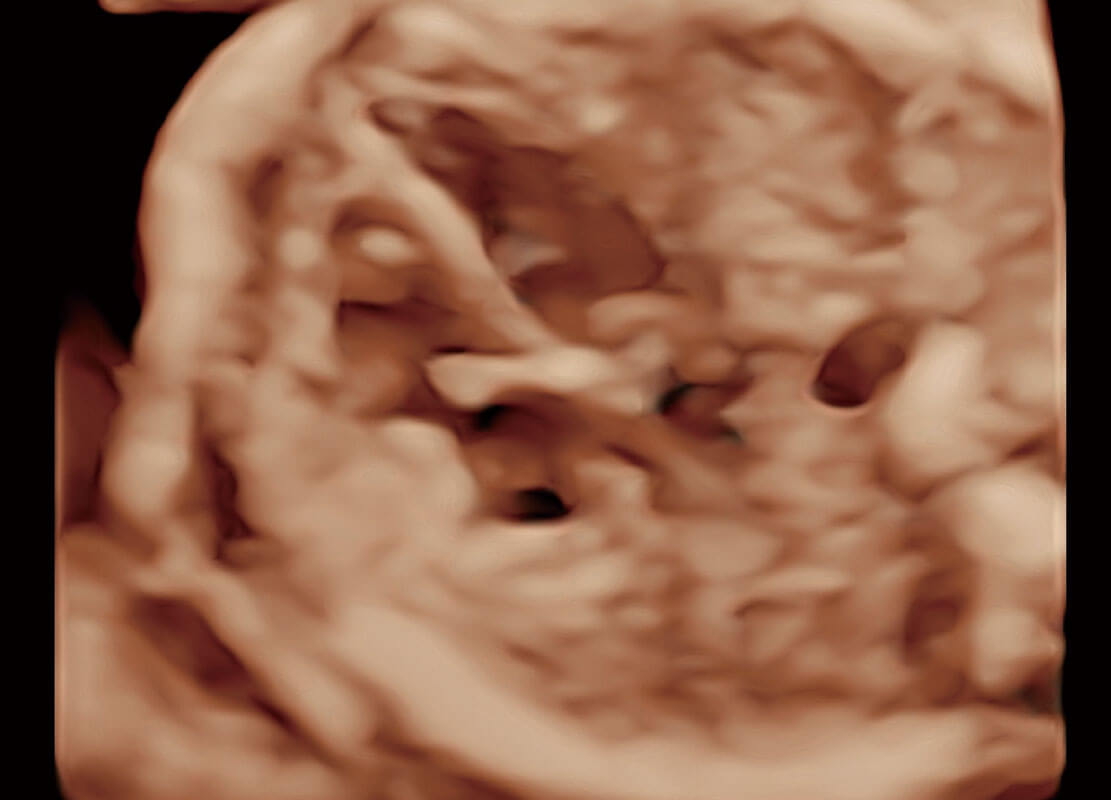

P60在胎儿早孕期超声筛查中为您带来优异的图像质量。

高分辨率容积成像-早孕胎儿

光影成像-孕囊